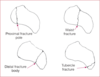

Bennett’s fracture

Oblique fracture at the base of the thumb metacarpal

Boxer’s Fracture

5th metacarpal fracture